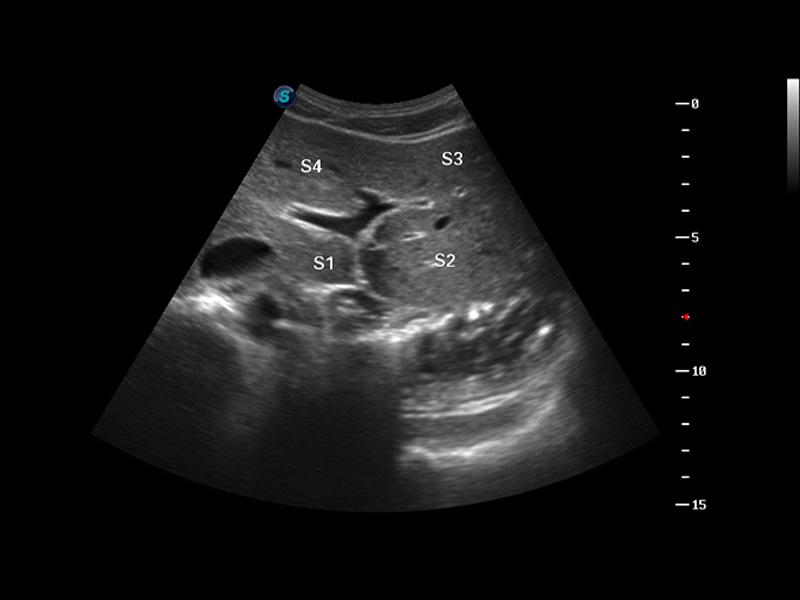

S8 EXP便携式彩色多普勒超声诊断仪是球速体育入口研发的高端全身应用型便携彩超。高通道的VIS平台融合可视化(Visual)、智能化(Intelligent)和人性化(Smart)的特点,配以球速体育入口自主研发生产的探头大家族,使您能够快速、准确的获得病人信息,提高工作效率的同时减轻疲劳。

成像技术

多波束形成器

μ-Scan微米成像

谐波成像

实时宽景成像

空间复合成像

3D/4D成像